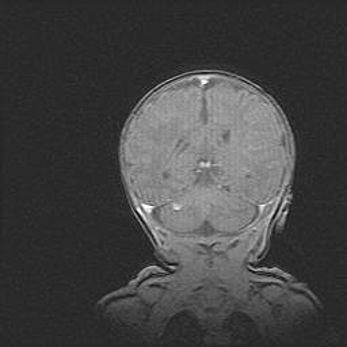

Мальформация Денди-Уокера. Киста задней черепной ямки.

Агенезия мозолистого тела.

Возраст: 2,5 месяца

Вес: 2420 г

Пол: женский

Окружность головы: 37 см

Срок гестации: 32 недели

Мальформация Денди—Уокера — редкий вид патологии ЦНС, представляющий собой врожденный порок развития каудального отдела ствола и червя мозжечка, ведущий к неполному раскрытию срединной (Мажанди) и латеральных (Лушка) апертур IV желудочка мозга. Для этогно синдрома характерна триада симптомов: гипотрофия червя мозжечка и/или полушарий мозжечка, кисты задней черепной ямки, гидроцефалия различной степени. В 70% случаев порок сочетается и с другими аномалиями головного мозга, в частности с агенезией мозолистого тела.